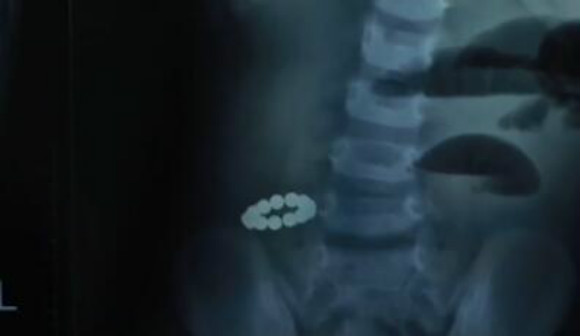

西安一男子尿道塞入28颗磁力球 称是睡梦中无

550x412 - 40KB - JPEG